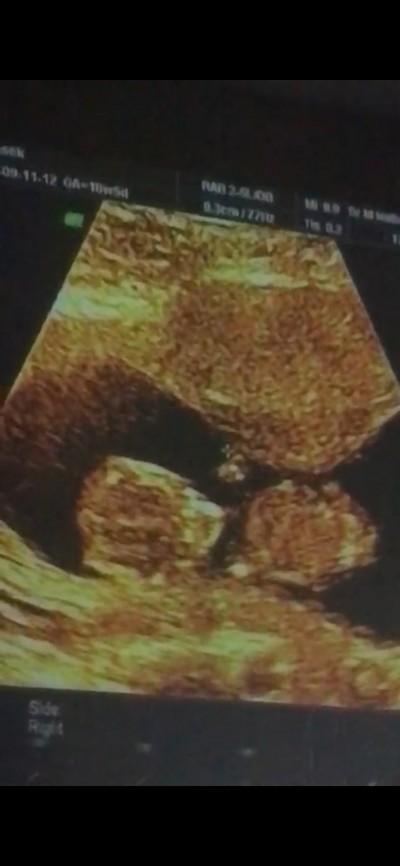

Arkadaşlar cinsiyet tahmini yapabilirmisyiz 10+5 gebeyim

Gebelik haftası 11+1

Hiç birşey belli degilki resimde bacak arası görünmesi lazım onu da yinede burda bilemeyebilirler postunda kapanır şimdi canım

Sırtı dönük bir küçükhanım sanki içime öyle doğdu:))